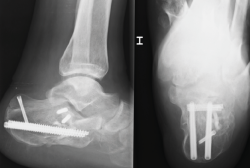

Figura 3. Varón de 59 años con fractura del calcáneo de Sanders de tipo IIA tras caída de 2 m de altura. Ángulo de Böhler precirugía de 6,3°, ángulo de Böhler poscirugía de 20,7° y a los 3 meses de 22,3°. No presentó ninguna complicación.

Cuando tenemos todos los fragmentos en su posición anatómica, habiéndose conseguido la reducción de la superficie subastragalina posterior, se fijan de manera provisional dichos fragmentos con agujas de Kirschner (aK) de 1,0 o 1,2. Estas aK fijan los fragmentos laterales de la fractura a la zona medial que normalmente está intacta. Se comprueba bajo fluoroscopio (proyección lateral) que se ha restablecido el ángulo de Böhler (Figura 3) y se fija de forma definitiva con 2 o 3 tornillos canulados de lateral a medial.

Figura 5. Varón de 37 años con fractura del calcáneo de Sanders de tipo IIB tras caída de altura. En la imagen de la tomografía computarizada se observa hundimiento de la zona lateral de la subastragalina posterior y un trazo posterior “en lengua”. Ángulo de Böhler precirugía de 8,5°.

A la hora de corregir el varo-valgo y la longitud del calcáneo colocamos un pin Steinmann o aK de 3,0 o 4,0 en la tuberosidad posterior y damos angulación varo o valgo (Figura 4) según necesite cada caso y siempre comprobando con la fluoroscopia (proyección axial). Una vez conseguida la angulación correcta, se fija de forma definitiva con 2 tornillos canulados de posterior a anterior (Figuras 5 y 6).

Figura 6. Se fijó con 2 tornillos canulados de lateral a medial, 2 tornillos de posterior a anterior y 1 tornillo cerrando el trazo en lengua. Ángulo de Böhler poscirugía de 30,9° y a los 3 meses de 32°. No presentó ninguna complicación.